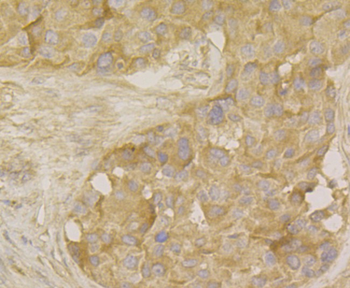

100 μl, 50 μl, 200 μl - HSC70 Mouse Monoclonal Antibody [orb704174]Featured

IF, IHC-Fr, IHC-P, WB

Human, Mouse, Rat

Mouse, Rat

Mouse

Monoclonal

Unconjugated

100 μl, 50 μl, 200 μl - ATF4 Recombinant Rabbit Monoclonal Antibody [orb704304]Featured